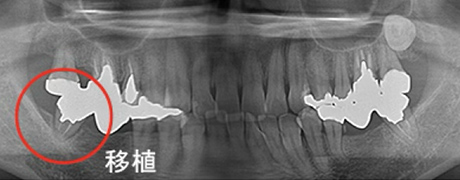

歯牙移植(歯の移植)

むし歯や歯周病で歯を失った後に、通常必要のない親知らずを、なくなった箇所に移植することによって健康な歯並びを回復する事ができます。

※移植には適合のための条件があります。

Before

After